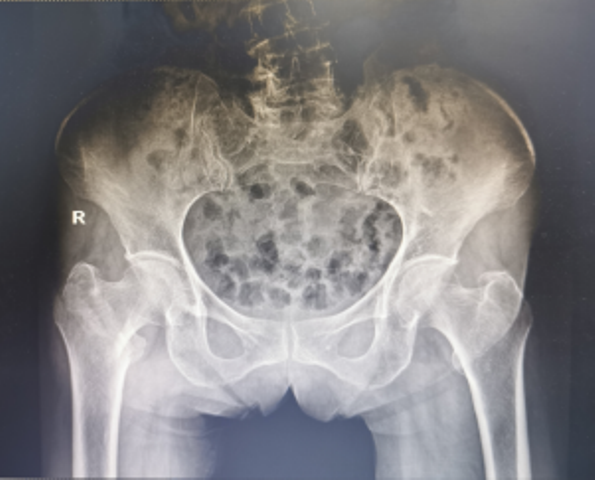

近日,陕西省第四人民医院骨科再次成功为一例91岁高龄的右股骨粗隆间骨折合并冠心病脑梗塞、贫血者实施右股骨粗隆间骨折闭合复位股骨近端抗旋转髓内钉内固定术(简称:PFNA内固定术)。经过术后精心的治疗与护理,患者现已转到康复医学科继续康复治疗。

3月19日,91岁高龄的万奶奶在家行走的时候不慎摔倒在地,当即感到右髋部剧烈疼痛,且不能行走。家属赶紧拨打医院120急诊电话,随后收治骨一科治疗,经检查确诊:右股骨粗隆间粉碎性骨折。